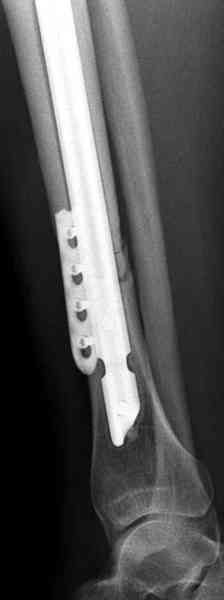

Недавно на нашей ежемесячной Morbidity&Mortality

conference мы разбирали похожий случай, ложный сустав большеберцовой кости после резекции опухоли.

К нашему онкологу-ортопеду обратился больной с жалобами на боли в голени, из рассказа - год назад была сделана биопсия большеберцовой кости, но название заболевания "не запомнил”.

Оперирован в военном госпитале с заменой сегмента

аллокостью большеберцовой кости и после демобилизации явился для постоянного наблюдения по месту жительства.

Наши имели проблему со сращением, пришлось им сделать динамизацию, дополнительную аутопластику.

Снимки представлены.